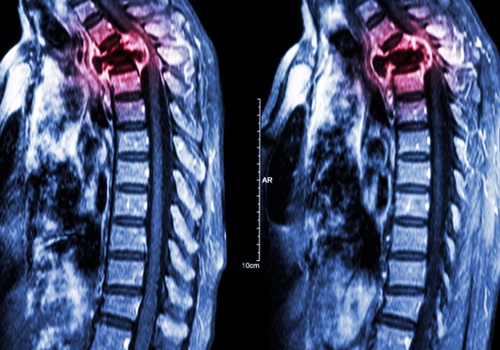

La tecnologia 3D, introdotta nella pratica clinica da pochi anni, permette di ricostruire in modo anatomicamente perfetto e con materiale robusto, ultra leggero e poroso il segmento osseo che si vuole sostituire (Figura 1). La TC tridimensionale permette infatti una precisa progettazione della protesi e la costruzione con la stampante 3D è perfetta. Il materiale ultraleggero non più liscio ma poroso, consente, oltre al fissaggio meccanico, un definitivo ancoraggio biologico, ottimale anche per le parti molli. Partendo da una TC 3D, con aggiunta di piccoli segmenti metallici, si stampa un pezzo poroso in titanio che è la copia esatta della parte da sostituire. Di struttura porosa sono anche i fittoni, le viti e gli steli da inserire e questo consente all’osso di crescere intorno alla protesi così da ottenere, oltre alla solita fissazione meccanica, una fissazione biologica, perché le strutture ossee incorporano la protesi e anche le parti molli si ancorano meglio. Le protesi 3D vengono usate soprattutto nei tumori di bacino, vertebre e scapola, ove non esistono protesi modulari (Figura 2). Oggi, dato che è in aumento la necessità di sostituire vecchie protesi d’anca che si sono usurate nel tempo, si usano anche per questa patologia benigna. Quanto ai costi, le protesi in 3D variano dagli 8.000 ai 12.000 euro. Anche se un po’ alti, rimangono comunque nei parametri standard. La Regione indirà presto una gara per le ditte che producono le protesi custom made e i costi dovrebbero diminuire.